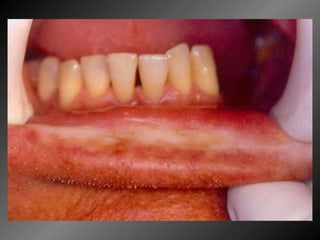

Granuloma Piogênico Lesão Nodular Séssil ou pediculada Avermelhada ou vinhosa Sangramento espontâneo e áreas de micro-ulceração superficial

Granuloma Piogênico Lesões nodulares de coloração avermelhada ou vinhosa Provavelmente uma reação inflamatória exagerada ao trauma menor Crescimento rápido, às vezes sangramento espontâneo Ocorre em qualquer idade mas parece mais freqüente em adultos jovens e adolescentes  Localização mais comum: gengiva (NEVILLE,2001)

Granuloma Piogênico Lesões mais antigas, são menos vasculares e mais fibrosas Papila interdental e regiões anteriores são áreas preferenciais, principalmente por vestibular (BORK,1996)

Granuloma Piogênico LesãoNodular Séssil ou pediculada Avermelhada ou vinhosa Sangramento espontâneo e áreas de micro-ulceração superficial

Granuloma Piogênico Lesõesnodulares de coloração avermelhada ou vinhosa Provavelmente uma reação inflamatória exagerada ao trauma menor Crescimento rápido, às vezes sangramento espontâneo Ocorre em qualquer idade mas parece mais freqüente em adultos jovens e adolescentes Localização mais comum: gengiva (NEVILLE,2001)

Granuloma Piogênico Lesõesmais antigas, são menos vasculares e mais fibrosas Papila interdental e regiões anteriores são áreas preferenciais, principalmente por vestibular (BORK,1996)